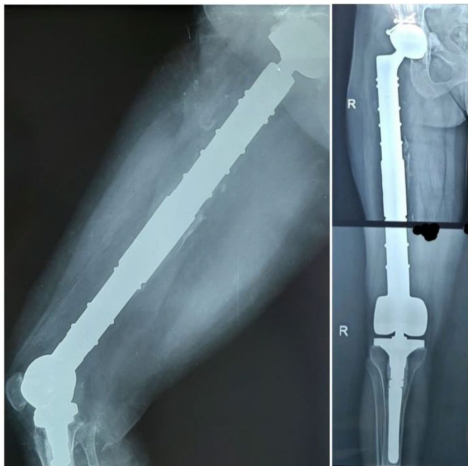

针对罕见但极具破坏性的骨包虫病(Osseous Hydatidosis),突尼斯研究团队提出创新性治疗方案:通过en bloc resection(整块切除)彻底清除病灶,结合mega prosthesis(巨型假体)重建肱骨与股骨功能。两例患者(肱骨全段感染、股骨近端广泛破坏)术后分别随访1.5年与5年,均实现无复发且肢体功能显著恢复(Constant肩评分65,Mayo肘评分70,LEFS下肢功能保留71.3%)。该研究为晚期骨包虫病的根治提供了类肿瘤外科治疗范式,显著降低48%的高复发风险。

突尼斯骨科团队针对两例晚期患者(45岁女性全肱骨感染、39岁女性近端股骨破坏)制定标准化流程: